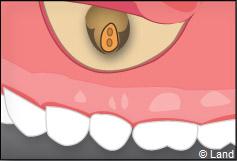

Une préparation de l’extrémité restante est effectuée à l’aide d’une petite fraise boule, de façon à recevoir une obturation canalaire étanche.

Un biomatériau et une membrane destinée à la régénération osseuse guidée peuvent être mis en place dans la cavité ainsi dégagée.

On repositionne le lambeau qui est ensuite suturé, et la radiographie de contrôle peut être prise.